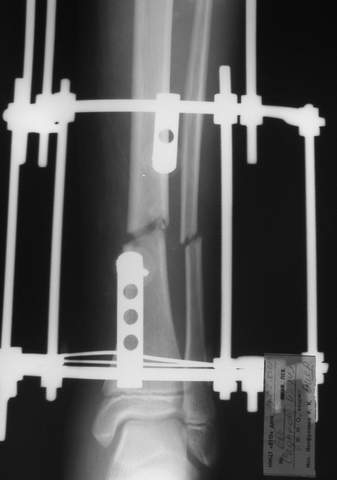

Под рукой прилагаемый пример. Как видите, "стриптиз-аппарат" (шутка проф. З.К.Башурова): 3 кольца-2 кольца-2 полукольца. В случае, который представил Евгений, характер повреждения позволил бы сразу использовать аппарат на основе 2 колец; в крайнем случае прокс. опора м.б. демонтирована сразу после репозиции.

LNS> Под рукой прилагаемый пример. Как видите,

Исходя из него главное преимущество "двух полуколец" - это полный объем сгибания в

коленном суставе, но...

незначительно он отличается от варианта "два кольца"...

В аттачтах №№ 1 и 2 - примеры, когда 2 кольца не позволили послеоперационно

исправить смещение фрагментов большеберцовой (по ширине и вальгусное).

А казалось бы (#2) - поиграй на штангах и все влетит.

1

1a

2

3a

3b

3c

В аттачте № 3 - один из примеров полукольцевого аппарат...